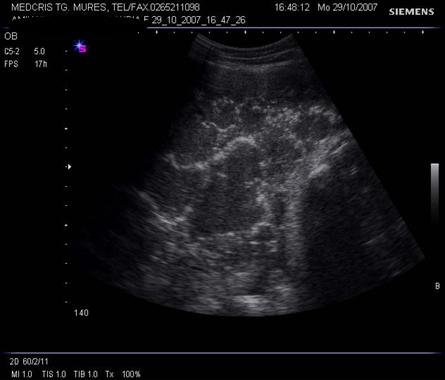

Sindromul de banda amniotica ( ADAM = amniotic deformity, adhesions, mutilations) se datoreaza unei rupturi precoce de amnion, urmata de separarea amniochoriala si punerea in contact a fatului cu chorionul. Atat chorionul expus, cat si restul suprafetei amnionului, produc bride mezodermale care se extind spre fat , dupa ce chorionul absoarbe lichid amniotic.

Incidenta intre 1/1200 si 1/10000 de nascuti vii.

Diagnostic ecografic: tipic oligohidramniosul este asociat cu benzi ecogene intre placenta sau peretele uterin si fat , cu restrictia miscarilor fetale.[9]

Spre deosebire de anomaliile genetice fetale, anomaliile induse de benzile amniotice sunt asimetrice.

Cazurile severe implica amputatii de degete sau membre, strangulatii ale creierului sau chiar prin compresie de cordon ombilical, moarte fetala in utero.

Cazurile severe au fost diagnosticate cel mai devreme la 24 de saptamani .[8]